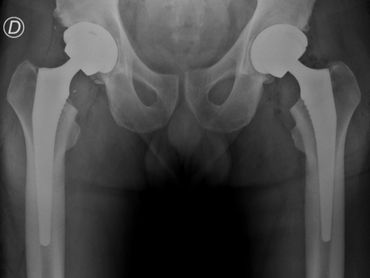

Reemplazo articular de ambas caderas en un tiempo